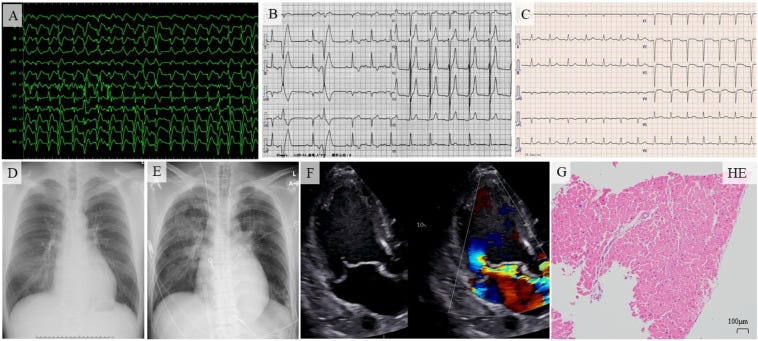

‘A 27-year-old man was transferred to the emergency room in cardiopulmonary arrest. The patient had just received the first dose of the mRNA-1273 severe acute respiratory syndrome coronavirus 2 (SARS-CoV-2) vaccine (Moderna, Cambridge, MA, USA) 8 days earlier and had no symptoms such as chest pain suspected of myocarditis or general fatigue suspected of low cardiac output after the vaccination until the emergency room visit. He had a high exercise habit; his teammates called for an ambulance when he was found sitting unconscious during practice. Upon arrival at the emergency room, he presented asystole. Despite cardiopulmonary resuscitation, fatal ventricular arrhythmias (Fig. 1A) repeated, and he eventually received venoarterial extracorporeal membrane oxygenation (VA-ECMO) and Impella CP (Abiomed, Danvers, MA, USA), after 2 h of his visit. A chest radiograph obtained in an emergency room showed an enlarged heart and pulmonary congestion (Fig. 1E). The patient had undergone orthopedic surgery 3 months before the recent hospitalization. An electrocardiogram (ECG) abnormality and mild cardiac shadow enlargement in chest radiograph had been noted preoperatively (Fig. 1B, D); however, since he was asymptomatic, no further examination was performed. Additionally, he had no family history of cardiovascular disease or sudden death.

On admission to the coronary care unit, blood pressure was 81/45 mmHg, pulse rate was 73/min, and the temperature was 37.2 °C with VA-ECMO at 2.2 L/min, noradrenaline at 0.4 μg/kg/min, and dobutamine at 1.0 μg/kg/min. The nasopharyngeal SARS-CoV-2 polymerase chain reaction test was negative. ECG showed sinus rhythm, right-axis deviation, and poor R-wave progression (Fig. 1C). Blood tests revealed severe liver and kidney dysfunction, lactic acidosis, elevated highly sensitive troponin I level, with no significant increase in eosinophil count. Transthoracic echocardiography showed that left ventricular end-diastolic diameter increased to 77 mm and left ventricular ejection fraction (LVEF) decreased to 25 %. Right ventricular contraction also decreased severely. The left ventricular wall thickness was 14 mm, slightly thickened, and there was a small amount of pericardial effusion. Furthermore, the posterior leaflet of the mitral valve was significantly prolapsed, which indicated severe mitral regurgitation (MR) (Fig. 1F). There was no evidence of vegetation or ruptured chordae tendineae. Coronary angiography showed normal coronary arteries, and we performed endomyocardial biopsy from the right ventricular side of ventricular septum and obtained three specimens. We considered the patient to have fulminant myocarditis developed in the presence of stage B heart failure due to chronic severe MR and started corticosteroid pulse therapy (methylprednisolone 1000 mg/day for 3 days) and intravenous immunoglobulin (IVIG) therapy (1 g/kg for 2 days). The results of the endomyocardial biopsy were no inflammatory findings in the myocardium in all three specimens (Fig. 1G). After initiation of ventricular assist devices with VA-ECMO and Impella CP, steroid pulse therapy, and IVIG therapy, cardiac enzyme level decreased (Fig. 2). He was able to wean off VA-ECMO on day 4; however, anisocoria appeared on the same day and head computed tomography revealed diffuse severe brain edema. On day 7, his LVEF improved to 45 %, and Impella CP was weaned. On day 9, the electroencephalogram became flat. The patient died on day 28 due to progressive multiorgan failure. The blood eosinophil count showed no significant increase until his death.